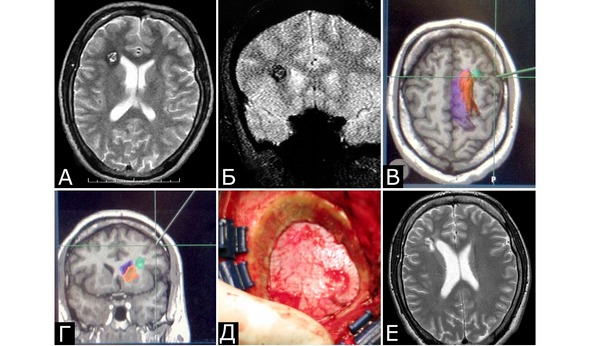

Рис. 56. Планирование доступа к небольшой кавернозной мальформации (0,5 см в диаметре) правой лобной доли с использованием МР-навигации. А, Б – МРТ до операции, режимы Т2 и Т2*, аксиальная и фронтальная проекции. В, Г – реконструированные по данным предоперационного пакета МРТ данные для МР-навигации, планирование доступа. Зеленым цветом отмечена КМ, оранжевым – базальные ядра, фиолетовым – боковой желудочек. Д – небольшая (2,5 см в диаметре) трепанация для доступа к КМ. Е – МРТ после операции, режим Т2

Больной Д., 17 лет (рис. 58).

Клинический диагноз: КМ задней центральной извилины слева. Состояние после кровоизлияния. Симптоматическая эпилепсия.

Течение заболевания и обследование: Начало заболевания за 2 месяца до госпитализации в виде тонических судорог в правой ноге. В течение последующих двух месяцев – около 20 аналогичных приступов. При МРТ выявлена КМ в области центральных извилин слева с признаками кровоизлияния (А, Б). При ЭЭГ – диффузная эпилептиформная активность с акцентом слева. При поступлении очаговая неврологическая симптоматика отсутствует.

Операция: После вскрытия ТМО при прямой стимуляции коры идентифицированы зоны «ноги» и «руки» (В). Энцефалотомия выполнена в соответствии с полученными данными. КМ удалена единым блоком (Г – этап удаления КМ). Выполнена частичная резекция измененного кровоизлияниями мозгового вещества. Резекция зоны глиальной гиперплазии вблизи от зоны ноги не проводилась.

Послеоперационное течение: В послеоперационном периоде нарастания неврологической симптоматики не было. При осмотре спустя 3 года после операции очаговой неврологической симптоматики нет. Сохраняются редкие парциальные приступы в виде тонических судорог в правой ноге. По данным МРТ, КМ удалена полностью (Д, Е). Рекомендован дальнейший постоянный прием антиконвульсантов.